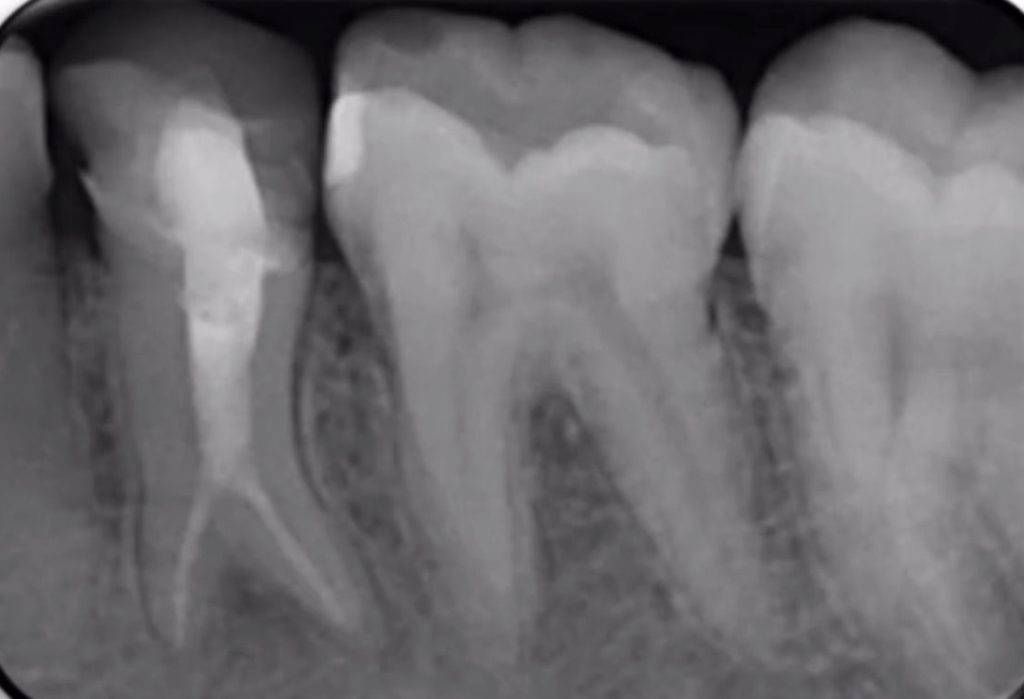

Fig. 1

Clinical and Radiographic Findings: Clinical assessment revealed sensitivity to percussion and palpation of the buccal mucosa. The initial periapical radiograph showed a short, poorly compacted previous filling and a distinct periapical radiolucency measuring approximately 3 mm in diameter. A radiolucent area along the distal root contour strongly suggested an uninstrumented canal. The diagnosis was Chronic Apical Periodontitis secondary to inadequate root canal treatment. Figure 1: Initial periapical radiograph showing inadequate obturation and apical radiolucency.